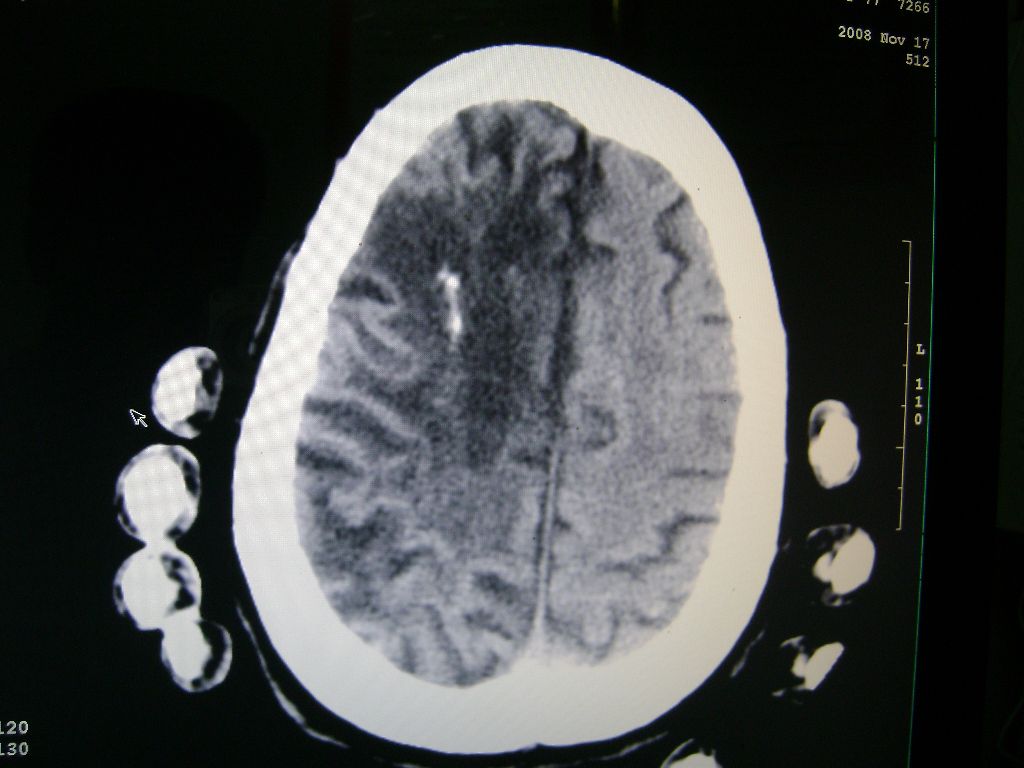

标题: CT16663:F 77 昏迷不醒,各位老师看咯! [打印本页]

f 77 昏迷不醒

出血性脑梗塞

出血性脑梗塞!

右侧额颞枕顶叶脑软化灶,脑萎缩,大脑中动脉壁钙化。

右脑软化灶,考虑再次梗塞,高密度灶出血?钙化?。。。量ct值,改窗宽,位

右脑软化灶,考虑再次梗塞,右顶叶高密度影不像是出血,密度很高,建议量ct值!

右侧半球陈旧性卒中,不除外伴有新病灶,左额叶梗塞,双侧大脑中动脉钙斑

右侧额颞枕顶叶脑软化灶,脑萎缩,大脑中动脉壁钙化。不支持出血(密度高,边界清且局限)顶枕区似有新发梗塞,建议核磁

1)右侧额颞枕顶叶脑软化灶;其内高密度影,多为钙化灶。2)脑萎缩。3)大脑中动脉钙化。

再次脑梗死,右侧额颞枕顶叶脑软化灶,高密度考虑钙化

右侧陈旧脑梗塞伴脑萎缩。脑内点状钙化。大脑中动脉壁钙化灶。无出血灶。

1)右侧额颞枕顶叶脑软化灶并钙化灶可能。2)脑萎缩。3)大脑中动脉钙化。 -